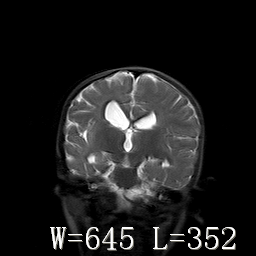

标题: PED3252:脑室增大。

女,3岁,3岁不会说话,阵发性抽搐、自伤。

考虑为梗阻性脑积水(中脑导水管狭窄)。

脑积水?脑发育不良?

侧脑室不规则,前后角尖角样,脑白质较少:考虑灰质发育不良可能

倒数第3附图不是这个病人的吧!考虑脑白质发育不良可能。

右侧额叶发育不良!

右侧额叶发育不良。

右侧额叶发育不良

考虑,脑发育不良,胼胝体发育不全?(图片不全,矢状位?)